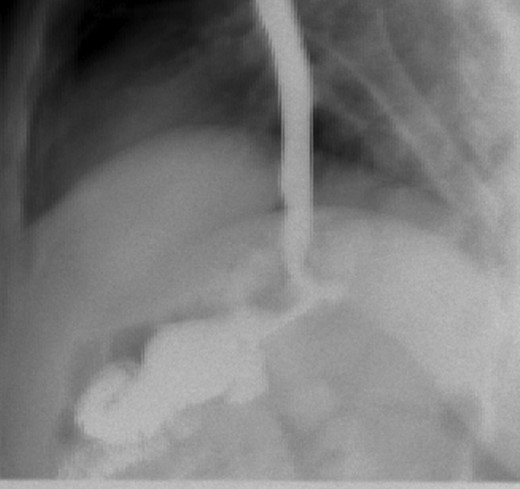

Second patient is a 35-year-old female with BMI 32.3 of with history of diabetes mellitus, hyperlipidemia who underwent LRYGB in June 2014, laparoscopic cholecystectomy 2014 was seen in the clinic for 1 year follow up. After having lost 54 pounds with right sided abdominal pain associated with nausea and vomiting. Patient had an upper GI which was negative and subsequently still continue to have the abdominal pain and undergone an EGD which was normal as well. At that point patient was lost to follow up for over a year as she moved to Florida and states while in Florida had CT scan of abdomen which showed questionable internal hernia at the anastomosis. Patient was seen and evaluated in our emergency room with complaints of right sided abdominal pain with nausea and vomiting. Vital signs were stable. On physical exam, tenderness in the epigastric area. All the labs findings were unremarkable. CT scan of abdomen did not show any abnormality. However, due to possibility for an internal hernia, patient was admitted and was taken to the operating room for diagnostic laparoscopy on November 2017. She was found to have long candy cane limb. We resected excessive redundant 4 cm length of the long blind jejunal loop of gastrojejunostomy anastomosis using Endo GIA Tri-Stapler device, Intra-op EGD was performed showing 4 cm gastric pouch. Post-operative course was uneventful. The patient was discharged to home on post-operative Day 4 and returned to clinic 1 week for follow up and tolerating diet and completely asymptomatic and pain free. Three weeks post laparoscopy patient had upper GI which was found to be normal (Figs 3 and 4).